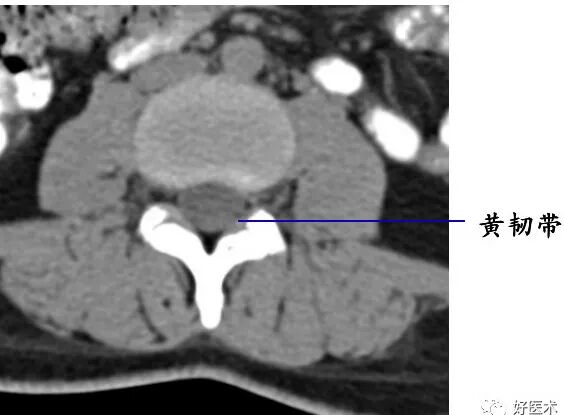

在相邻椎骨的椎弓之间的叫椎弓间韧带,由弹性结缔组织构成,呈黄色,故又称黄韧带。

后壁:椎板、黄韧带

黄韧带较厚(正常时≤3 mm),位于椎板和关节突的内侧面,密度高于硬脊膜囊和硬膜外脂肪,显示较清晰